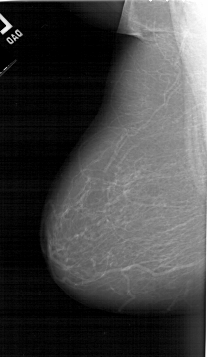

A_1255_1.LEFT_MLO

LEFT_MLO LINES 6421 PIXELS_PER_LINE 3736 BITS_PER_PIXEL 12 RESOLUTION 43.5 NON_OVERLAY

RIGHT_MLO LINES 6241 PIXELS_PER_LINE 3766 BITS_PER_PIXEL 12 RESOLUTION 43.5 OVERLAY

FILE: A_1255_1.RIGHT_MLO.OVERLAY

TOTAL_ABNORMALITIES 1

ABNORMALITY 1

LESION_TYPE MASS SHAPE IRREGULAR MARGINS ILL_DEFINED

ASSESSMENT 5

SUBTLETY 4

PATHOLOGY MALIGNANT